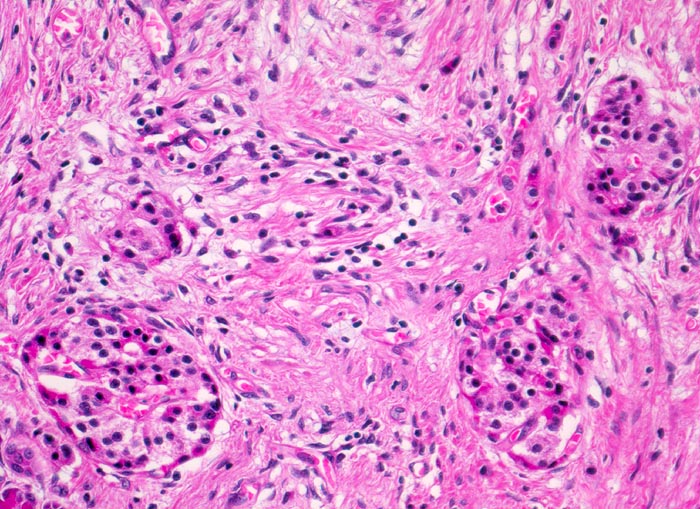

Chronisch-sklerosierende Pankreatitis

Während die Azini das exokrine Pankreasparenchym zunehmend fibrosieren und schliesslich ganz verschwinden, bleibt das endokrine Pankreas relativ gut erhalten. Nach Verschwinden der Azini sind im fibrosierten Gewebe Pankreasinseln zurückgeblieben. Geringgradiges lymphoplasmazelluläres Entzündungsinfiltrat.

Alkoholiker mit rezidivierten akuten Pankreatitisschüben. Chronische Diarrhoe.

Durch das Verschwinden des exokrinen Pankreas rücken die Inseln näher zueinander und erscheinen zahlreicher als normal. Dies führt zum fälschlichen Eindruck einer Hyperplasie der Pankreasinseln.

Histologie

200